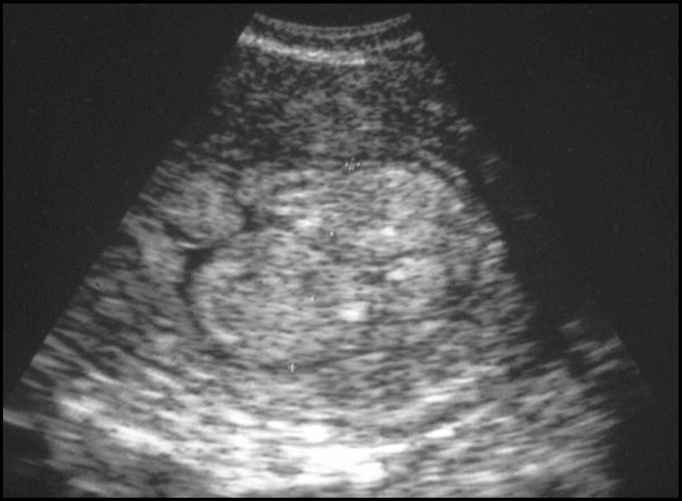

Cancer de l’endomètre. Epaississement global souvent important (15 à 30 mm)

Hétérogène avec ou sans zones de nécrose, caillots, disparition de la ligne cavitaire